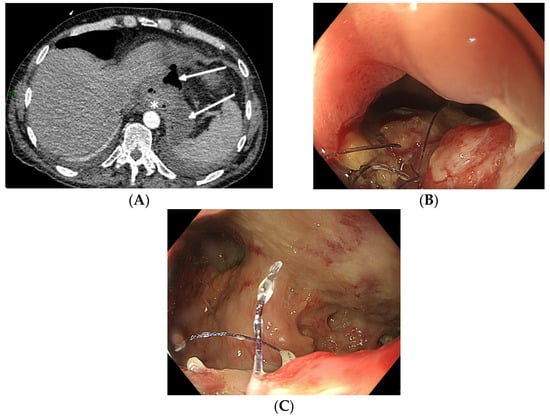

5.3. Post-Procedure Difficulties

6. Adverse Events Relating to EVT in the Upper Gastrointestinal Tract